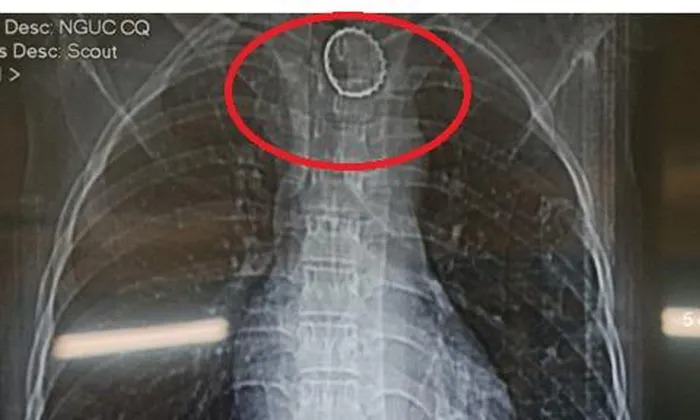

Tại đây, qua nội soi tiêu hóa, các bác sĩ phát hiện một dị vật nghi là 1 nắp chai nước giải khát, đường kính khoảng 3cm cắm vào thành thực quản, niêm mạc xung quanh phù nề, giữ chặt dị vật. Trên phim X-quang và CT-scan ngực cho thấy hình ảnh dị vật cản quang ở thành sau thực quản đoạn 1/3 trên cách cung răng khoảng 20cm. May mắn là dị vật chưa làm thủng thực quản gây tràn dịch màng phổi hoặc viêm trung thất.

Dị vật cản quang ở thành sau thực quản đoạn 1/3 trên cách cung răng khoảng 20cm.